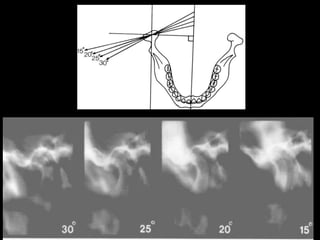

 Schüllers Technique

 Sagittal view of Lateral part of the condyle

and temporal components

 X-ray directed parallel to long axis of condyle

 Film is positioned against facial skin on side of

interest parallel to sagittal plane

 X ray tube head is projected from opposite side

 Central beam is projected downwards 25⁰ and

centered on T.M.J.

 Central beam is projected through cranium above

petrous ridge of temporal bone on film side

through T.M.J. in line with long axis of condyle

 Horizontal angle not more than 10⁰

 Vertical angle not more than 25⁰

Tracing of angles between the long axis of each condyle and the midsagittal plane.

For tomography views the patient is rotated according to the measured angles to

produce an undistorted radiographic view of each T.M.J.